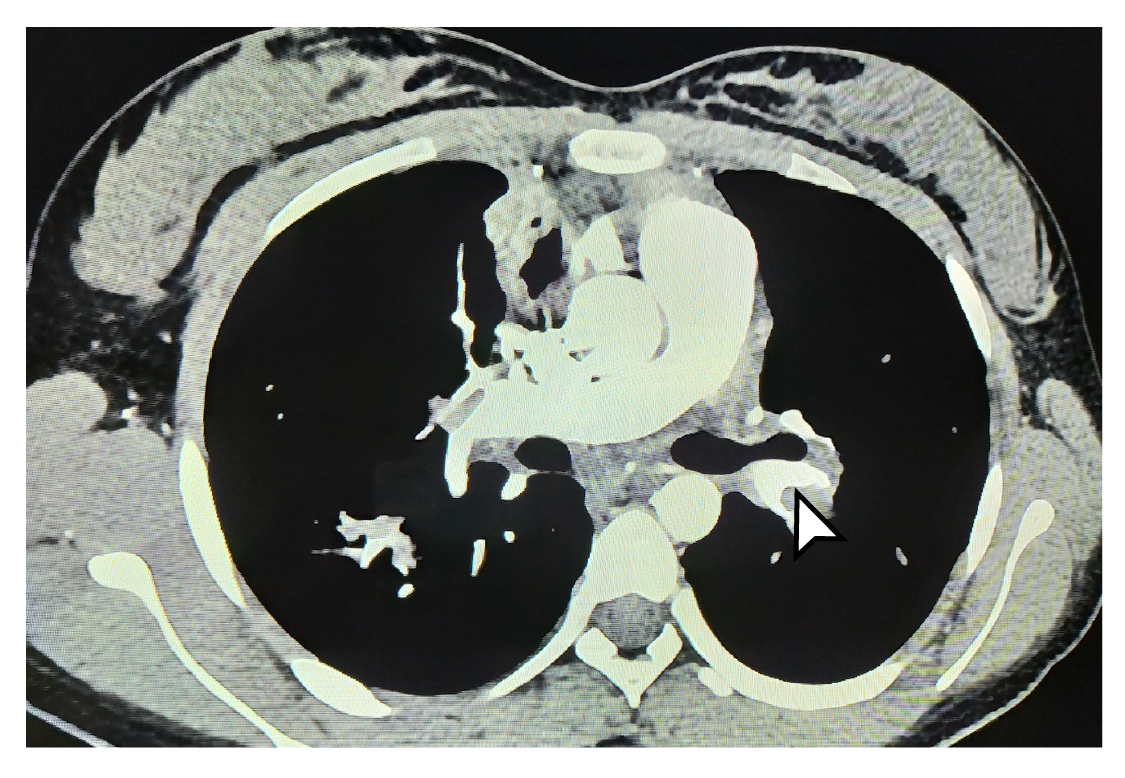

Los estudios se complementaron con tomografías de tórax y de abdomen con contraste, las cuales evidenciaron tromboembolia pulmonar grave (figuras 1 y 2) con múltiples trombos bilaterales, áreas pequeñas de infartos pulmonares, nódulos pulmonares múltiples, y embolia venosa renal bilateral con trombo que comprometía la vena cava superior. Se decidió reiniciar el tratamiento anticoagulante con heparina de bajo peso molecular, con lo cual los síntomas respiratorios mejoraron, lo que permitió dar de alta a la paciente y retomar el seguimiento por consulta externa.